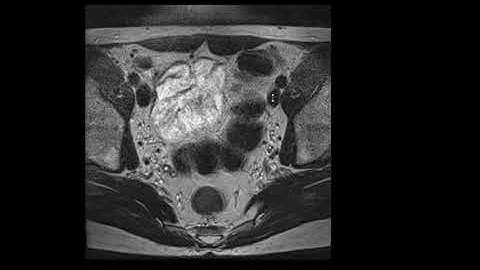

How to MRI of Pelvis | Positioning & Planning Tutorial